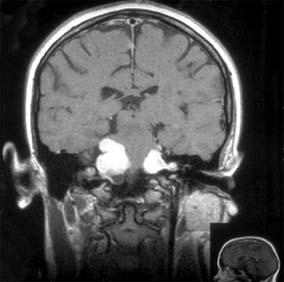

Figure 14-10

Figure 14-10: Cerebral hemisphere white matter lesions on MRI associated with acute demyelinative optic neuritis.

During an acute episode of optic neuritis, MRI shows gadolinium enhancement, increased signal on short tau inversion recovery (STIR) sequences, and sometimes swelling of the affected nerve. Brain MRI will show lesions consistent with demyelination in as many as 25% of patients with isolated optic neuritis (Figure 14-10). This does not establish a diagnosis of multiple sclerosis, though it does indicate a significantly increased risk of subsequent development of clinically definite multiple sclerosis. The value of steroid treatment in delaying the development of multiple sclerosis is greater in patients with abnormal brain MRI at presentation. Thus, brain MRI may be indicated in isolated optic neuritis if more precise information is wanted about the risk of multiple sclerosis and the value of systemic steroid treatment.